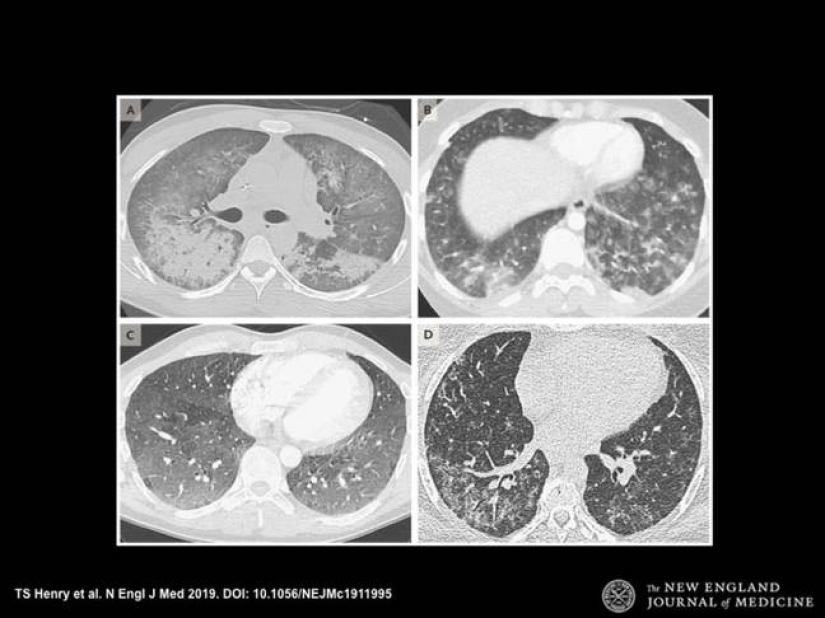

Los médicos decidieron publicar radiografías de los pulmones de los fumadores después de una serie de muertes asociadas con el uso del vapeo para advertir a todos sobre su daño.

Un pasatiempo de moda lleva a los jóvenes a la tumba, que están felices de inhalar humo fragante. Inofensivo, a primera vista, el enamoramiento conduce a consecuencias irreversibles. Las radiografías de los pulmones de los fumadores de vape son una prueba irrefutable del daño de las cachimbas electrónicas. Esperamos que esta información aparezca en su cabeza antes de la próxima calada.